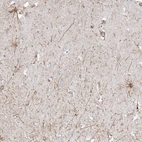

Immunohistochemical staining of human cerebral cortex shows positivity in neuronal processes.